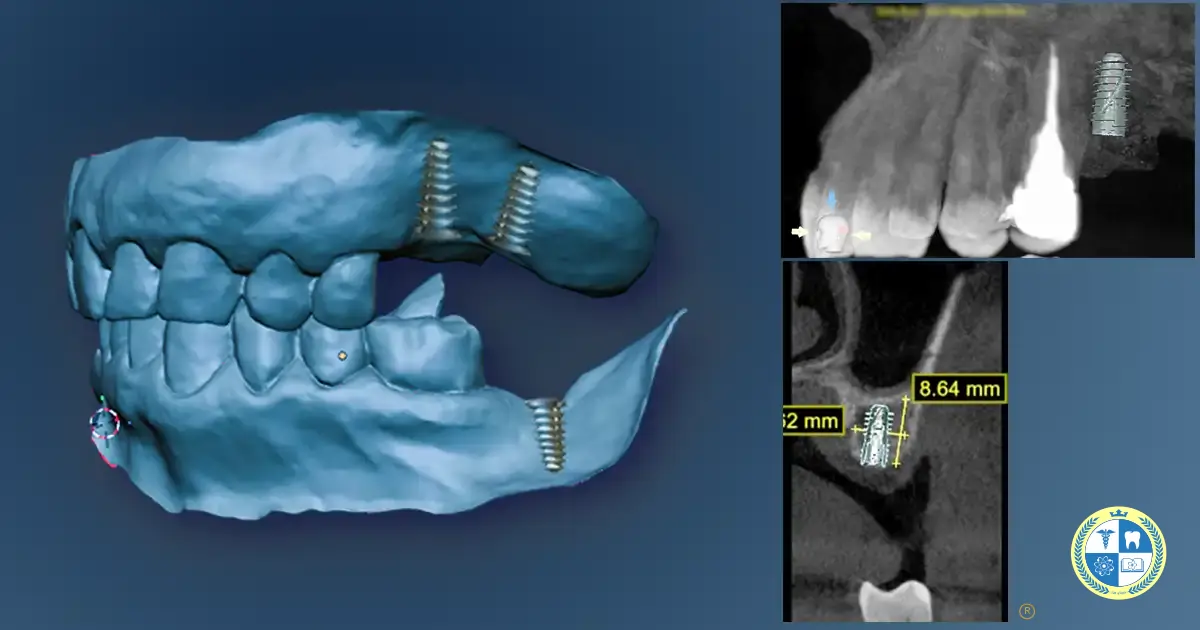

Primero definimos qué diente falta, qué hueso queda, cómo está la encía, qué ocurre con el espacio protésico y qué exigencia funcional tendrá la restauración. En algunos casos bastan radiografías convencionales; en otros se requiere imagen 3D para decidir con más precisión la posición y viabilidad del implante.